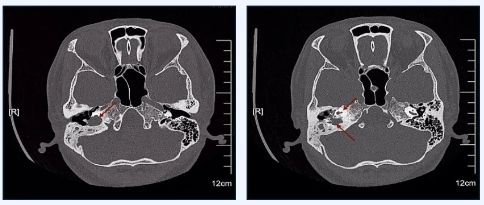

一周前,自幼右耳失聪的白雪(化名)找到了周彬主任,讲述7年前开始受到右耳反复流脓的困扰,有时还有耳鸣,3年前出现眩晕症状,而近1个月以来,眩晕更是发作了3次,每次持续3-4小时。周彬主任在门诊初步检查后,诊断为右侧中耳胆脂瘤,将其迅速收入院,并进行了全面的检查。这一看可真吓人,白雪的病情比预估的更加严重,中耳CT显示白雪的中耳胆脂瘤不仅长得大,关键是位置太特殊,正常大部分胆脂瘤们于迷路的外侧,而白雪的胆脂瘤主体位于耳蜗后内侧及面神经垂直段的内侧,导致面神经骨管和耳蜗的底转破坏严重,内下方与颈总动脉之间已没有骨性间隔。幸运的是,目前白雪还没有出现面瘫的症状,但是如果不及时手术治疗,后果将不堪设想!